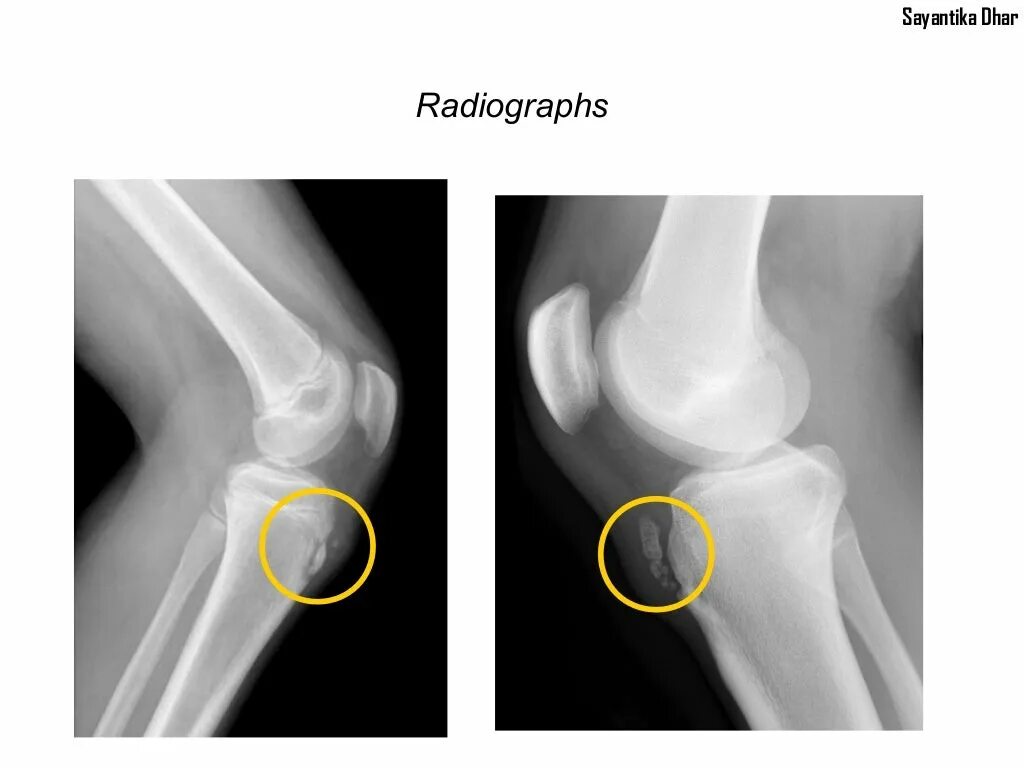

Болезнь шляттера код по мкб